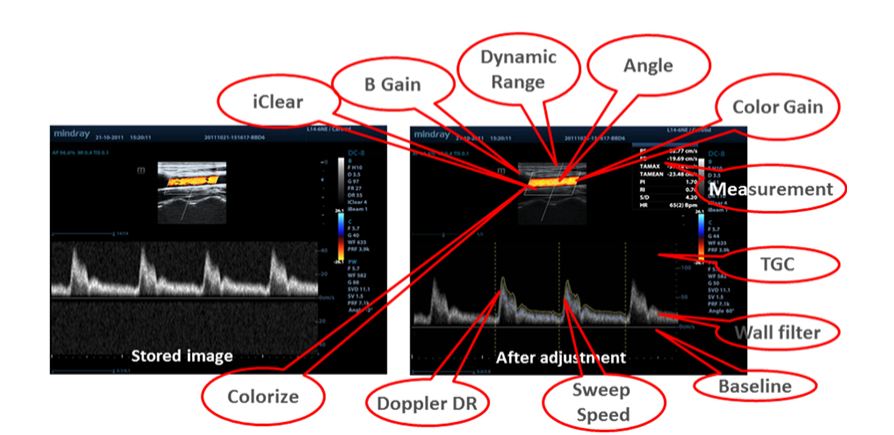

Raw Data

Enables optimum flexibility for post processing of the stored images including parameter adjustments, adding comments and measurements, allowing maximum productivity during scanning.